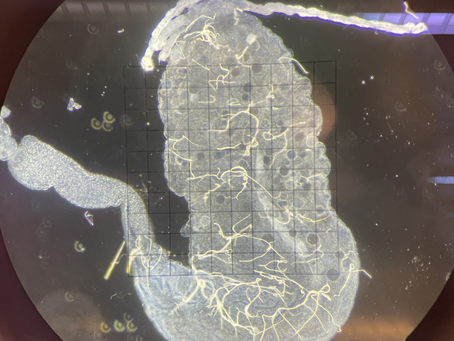

Getting Research-y

Over the summer after my first year at UW, I started my job as a Student Helper in a lab at the Seattle Children's Hospital Research...